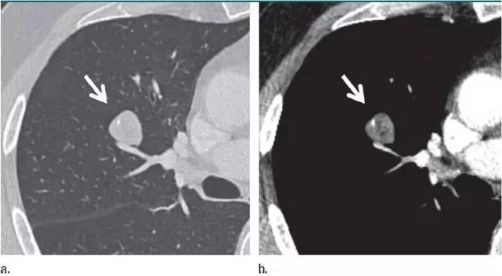

没想到我这么大岁数,切掉一个肺叶的十年后,再次做这么复杂的手术还这么顺利。 D大爷今年72岁,10年前曾行左肺上叶切除+淋巴结清扫术,手术标本病理为腺癌,术后给予了四次化疗。当时的胸部CT即可见右肺上叶小结节影,术后定期复查,病灶缓慢增大,一度略有缩小,此后再次逐渐增大。结合患者一直随访的影像学资料,杨如松院长考虑为右上肺新发恶性肿瘤。 2015年胸部CT 2020年胸部CT 虽然患者及其家属手术的意愿非常强烈,但此手术难度较高,原因在于: 1.患者年龄较高,手术风险大。 2.患者10 年前肺癌手术切除左边肺的一半,肺功能丧失较多。 3.病灶在右上肺的深部,切除有一定的难度。 为了保证患者术后的生活质量,我们不能够做肺的楔形切除这样的简单肺手术,而需要行肺段的切除。 EDDA重建提示病灶位置深 如果放在以前该患者就只能做做放化疗等保守治疗了。幸亏南京胸科医院目前引进了各种国内乃至国际上的先进技术。 如EDDA术前三D成像技术;只有单一3cm长切口的单孔胸腔镜技术;近红外荧光镜肺段、亚肺段精准定位技术等。 有了这些技术,杨如松院长心中有了底气。杨院长根据病人的情况设计手术方案,尽量减轻手术创伤,让接受第二次肺部复杂手术的高龄病人能够耐受,并且在术后能够顺利恢复。 根据术前EDDA三维重建,患者进行了单孔荧光胸腔镜S1a+2a切除术,术中先用ICG反染法确定段间面,再用膨胀萎陷法印证段间面,这保证了手术切除的精准性。 患者术中快速病理为贴壁型腺癌,这也印证了杨如松院长术前对患者肺结节良恶性的判断。 术后5天,D大爷非常顺利的出院了。出院前开心的窦大爷连声感谢杨如松院长:没想到我这么大岁数,切掉一个肺叶的十年后,再次做这么复杂的手术还这么顺利,谢谢、谢谢! 基本情况

手术方案